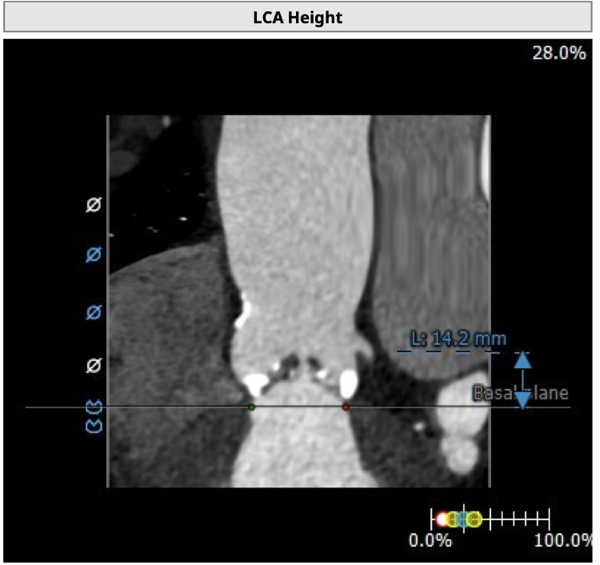

左冠开口高度14.2mm,右冠开口高度18.4mm,左右冠脉高度可。